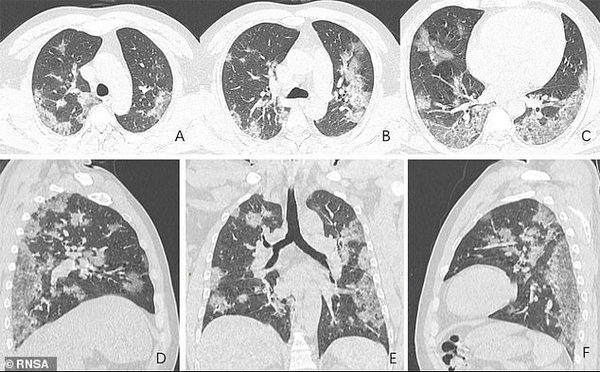

Так в сети появились рентгеновские снимки и сканы компьютерной томографии с изображением легких, которые принадлежали заболевшему коронавирусом. Радиологическое общество Северной Америки опубликовало снимки легких 44-летнего жителя Китая, работавшего на рынке в Ухане и умершего от COVID-19.

На фото видны все увеличивающиеся со временем белые пятна в нижней части дыхательных органов. Радиологи называют это симптомом "матового стекла", который отражает различные патологические изменения в легочной ткани.

Отмечается, что на фото заметно присутствие жидкости в легких мужчины, которое постепенно становится все более выраженным (проследить можно по изображению).